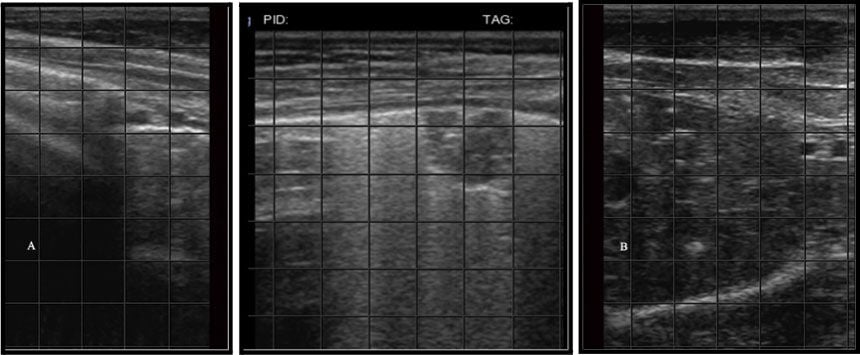

kAmp ?@C>2= =F?8 :D 2:C\7:==65 2?5 2AA62CD @? E96 F=EC2D@F?5 :>286 2D 2 D6C:6D @7 9@C:K@?E2= H9:E6 =:?6D \\ 42==65 C6G6C36C2E:@? 2CE:724E \\ E92E >@G6 324< 2?5 7@CE9 2D E96 42=7 3C62E96D] %96 >@DE DFA6C7:4:2= @7 E9@D6 9@C:K@?E2= =:?6D[ E96 A=6FC2= =:?6[ C6AC6D6?ED E96 3@F?52CJ 36EH66? E96 496DE H2== 2?5 E96 DFC7246 @7 E96 =F?8] p D>@@E9 4@?E:?F@FD A=6FC2= =:?6 :?5:42E6D 962=E9J =F?8 E:DDF6]k^Am

kAmr@>6E E2:=D 2C6 G6CE:42= 3C:89E H9:E6 =:?6D E92E 6>2?2E6 5@H? 7C@> E96 DFC7246 @7 E96 =F?8] }@C>2= =F?8D >2J 92G6 2 76H 4@>6E E2:=D[ 3FE E96 AC6D6?46 @7 D6G6C6 5:77FD6 4@>6E E2:=:?8 :D DF886DE:G6 @7 :?E6CDE:E:2= 5:D62D6 5F6 E@ :?4C62D65 7=F:5 @C 46==F=2C 244F>F=2E:@? H:E9:? E96 =F?8 E:DDF6] x?E6CDE:E:2= 5:D62D6 42? C6DF=E 7C@> D6AE:46>:2[ G:C2= :?764E:@?[ @C AF=>@?2CJ 656>2 7C@> 962CE 72:=FC6[ 7=F:5 @G6C=@25[ @C 2?2A9J=2I:D]k^Am

kAm{F?8 4@?D@=:52E:@? :D 2 4@?5:E:@? :? H9:49 A2CE @7 E96 =F?8 92D =@DE :ED ?@C>2= 2:C 4@?E6?E 2?5 364@>6 7:==65 H:E9 :?7=2>>2E@CJ 563C:D] &=EC2D@F?5 :>286D H:== D9@H 4@?D@=:52E65 2C62D 2D D@=:5 8C2J 2C62D E92E =24< E96 H9:E6 9@C:K@?E2= =:?6D EJA:42= @7 C6G6C36C2E:@? 2CE:724E] %96 D6G6C:EJ D4@C6 :D 56E6C>:?65 3J E96 D:K6 2?5 6IE6?E @7 4@?D@=:52E:@?]k^Am

kAm!=6FC2= 677FD:@?D 2C6 7=F:5 244F>F=2E:@? 36EH66? E96 =F?8 2?5 E96 496DE H2==j 23D46DD6D 2C6 C@F?5 6?42ADF=2E65 7=F:5 2?5 82D\7:==65 A@4<6EDj ?64C@D:D 2C6 D@=:5 ?@?\6?42ADF=2E65 A@4<6ED H:E9:? 4@?D@=:52E65 =F?8] p== 2C6 @E96C =6D:@?D E92E 42? 36 56E64E65 @? =F?8 F=EC2D@F?5D] !=6FC2= 677FD:@?D 92G6 >F=E:A=6 42FD6D 2?5 D9@F=5 36 :?E6CAC6E65 :? 4@?;F?4E:@? H:E9 2 E9@C@F89 A9JD:42= 6I2>:?2E:@? @7 E96 42=7] p3D46DD6D 2?5 ?64C@D:D :?5:42E6 49C@?:4 =F?8 5:D62D6[ H9:49 @7E6? 42CC:6D 2 A@@C AC@8?@D:D]k^Am

kAm%96 =F?8 D4@C:?8 DJDE6> EJA:42==J C2?86D 7C@> _ E@ d 32D65 @? E96 2AA62C2?46 @7 =F?8 E:DDF6 :? E96 F=EC2D@F?5 :>286] %@ AC@A6C=J D4@C6[ E96 @A6C2E@C >FDE C64@8?:K6 E96 5:776C6?46 36EH66? 2:C\7:==65 =F?8[ 2:C\7:==65 =F?8 H:E9 5:77FD6 A=6FC2= C@F896?:?8[ =@3F=2C =F?8 =6D:@?D 2?5 =@32C =F?8 =6D:@?D] x? E96 4@?E6IE @7 E96 &]$] D4@C:?8 DJDE6>[ =@3F=2C 2?5 =@32C =6D:@?D D:>A=J C67=64E E96 6IE6?E E@ H9:49 E96 =F?8 =@36 :D 4@?D@=:52E65 @? E96 F=EC2D@F?5 :>286] {@3F=2C =6D:@?D 2C6 C6=2E:G6=J D>2== 5:D4C66E 2C62D @7 4@?D@=:52E:@? H:E9:? 2? @E96CH:D6 26C2E65 =F?8 =@36] x? @E96C H@C5D[ E96 3C:89E H9:E6 A=6FC2= :?E6C7246 H:E9 C6G6C36C2E:@? 2CE:724E @7 ?@C>2= =F?8 42? 36 D66? 3@E9 23@G6 2?5 36=@H E96 =@3F=2C =6D:@? H96? E96 AC@36 :D A=2465 G6CE:42==J H:E9:? E96 C:3 DA246] {@32C =6D:@?D :?5:42E6 7F== E9:4<?6DD 4@?D@=:52E:@? @7 E96 =F?8 =@36 E92E 6IE6?5D AC@I:>2==J 7C@> E96 E:A @7 E96 =@36] x? E96 &]$] :>286[ E96 6?E:C6 5:DE2= =F?8 =@36 :D G:D:3=6[ H:E9 E96 8C2J A2C6?49J>2[ 2?5 E96 26C2E65 =F?8 42??@E 36 D66? G6?EC2= E@ E96 =6D:@?]k^Am